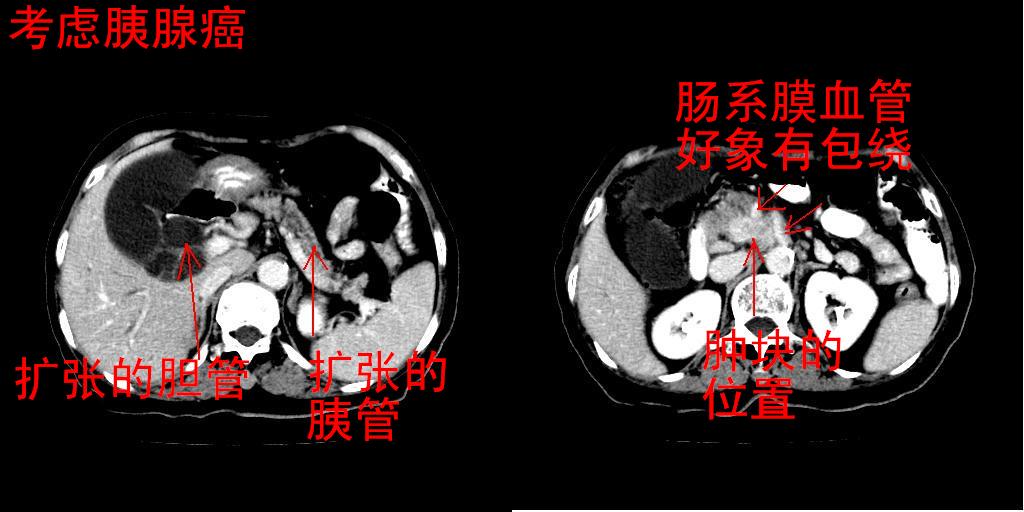

女,74岁,上腹部不适、腹胀两月余,黄染四天。请大家看看肿块周围血管情况。

肝内外胆管增粗,梗阻点位于胰头部,胰头增大,轻度不均性强化(较正常胰腺强化低,胰体尾呈退化';羽毛状';),孝虑为胰头ca.

肝内外胆管和胰管扩张,胆囊明显增大,胰头外形增大,无强化,考虑:胰头癌伴肝内外胆管、胆囊扩张积液。

肝内外胆管及胆囊扩张,胰管扩张,但“双管征”不明显,胆总管下段内见软组织有强化影,肠系膜上静脉推移不是很明显,考虑胆总管下段癌可能大。

胆总管.胰管扩张

胰头癌